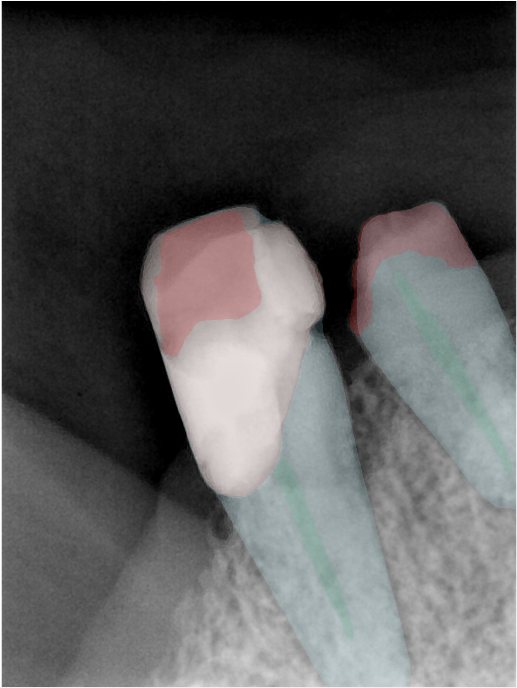

CR/DR 牙齿分割阶段记录

当前进展

- 完成了 CR/DR 牙齿相关分割训练

- 当前结果已经达到阶段预期,但仍有细节问题需要继续处理

相关测试

遇到的问题

- 训练过程中出现过 mask 下移问题

- 部分结果会出现 box 填充异常

- mask 边缘仍然有比较明显的锯齿感

参考

第二版算法问题测试